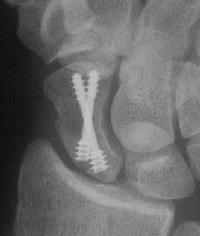

Clinical Example: Scaphoid fixation with more than one Herbert screw

A few years ago, I started putting in two Herbert screws for scaphoid fractures, with the thought that it would provide more rigid fixation. I think that it is helpful in some, but not all cases. Here are some of my results with a few variations...

1. Nondisplaced fracture in a surgeon who declined continuous immobilization.

One week after screw stabilization using a limited dorsal approach, he was back operating, but splinted when not scrubbed. These films are one month post op: no visible fracture.